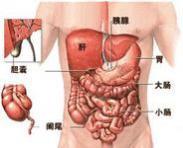

腹裂

628健康网为您分享有关腹裂的症状,腹裂的治疗方法,腹裂的预防知识,腹裂的症状图片,腹裂吃什么药,腹裂怎么治疗,腹裂患者食...

梅克尔憩室

628健康网为您分享有关梅克尔憩室的症状,梅克尔憩室的治疗方法,梅克尔憩室的预防知识,梅克尔憩室的症状图片,梅克尔憩室...

脐膨出

628健康网为您分享有关脐膨出的症状,脐膨出的治疗方法,脐膨出的预防知识,脐膨出的症状图片,脐膨出吃什么药,脐膨出怎么治...

先天性小肠闭锁和肠狭窄

628健康网为您分享有关先天性小肠闭锁和肠狭窄的症状,先天性小肠闭锁和肠狭窄的治疗方法,先天性小肠闭锁和肠狭窄的预防...

外伤性脾破裂

628健康网为您分享有关外伤性脾破裂的症状,外伤性脾破裂的治疗方法,外伤性脾破裂的预防知识,外伤性脾破裂的症状图片,外...